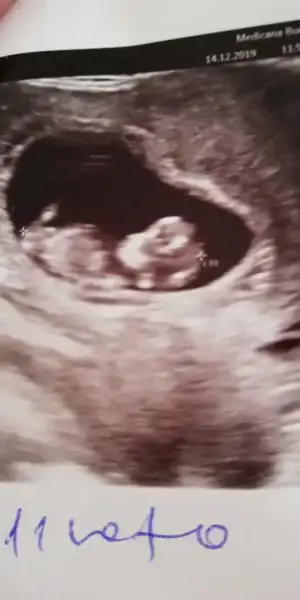

Dün doktora sordum erken dedi siz nasıl anladınız keşke bende görsem

Diger konumun başlıgında açıklama var dr görmeden nub teorinde siz görünüzDün doktora sordum erken dedi siz nasıl anladınız keşke bende görsem

Bu konuya baktım ben ama işte insan yinede anlayamıyor kemik yapısından da anlaşılıyor sanırımDiger konumun başlıgında açıklama var dr görmeden nub teorinde siz görünüz

Maalesef elimde ayrı günlerde çekilmiş iki usg tek var cuma günü gideceğim doktora bakalım okursa onu paylaşırım.Başka usg varmı 11 yada 12 hafta kız gibi ama emin olamıyorum

Net degil usg gördügüm nub ise erkek gibi başka varsa usg 11 yada 12 hafta paylaşın bu usg kaç haftalıkbanada tahminde bulunurmusunuz rica etsem